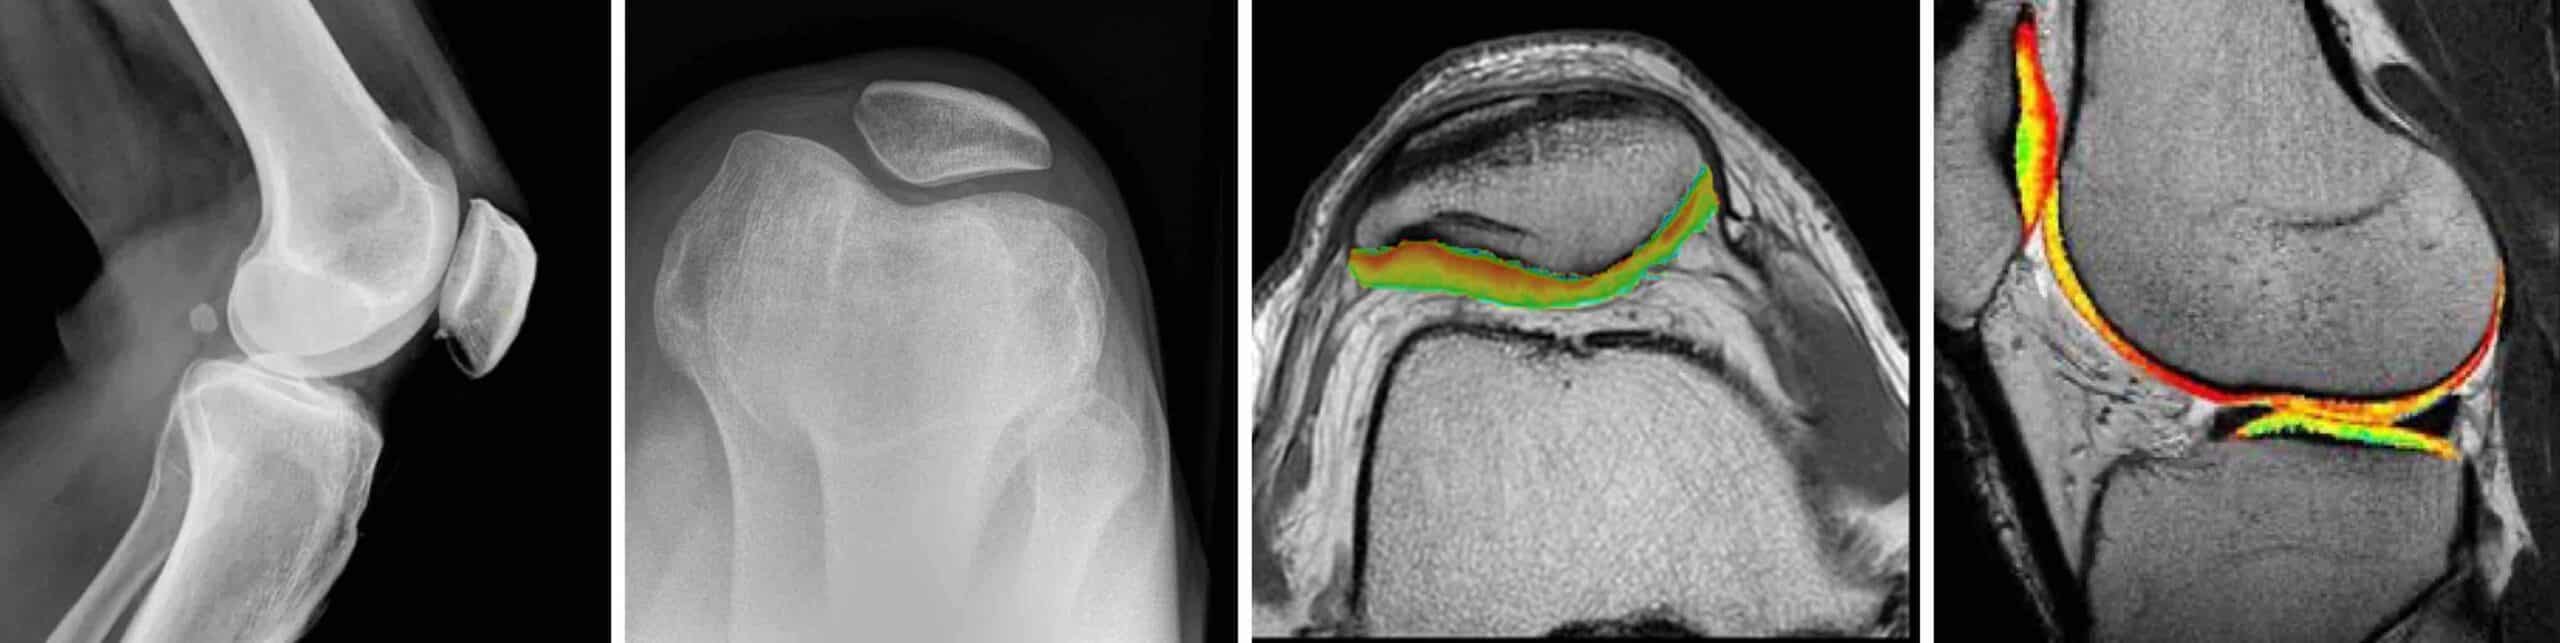

O diagnóstico de condrite no joelho é feito pela história clínica, exame físico do joelho e exames complementares de imagem. A ressonância magnética é o melhor exame para se diagnosticar a condrite. Uma sequência do exame de ressonância magnética, chamada de cartigrama, mapeia com diferentes cores a ultraestrutura condral do joelho.